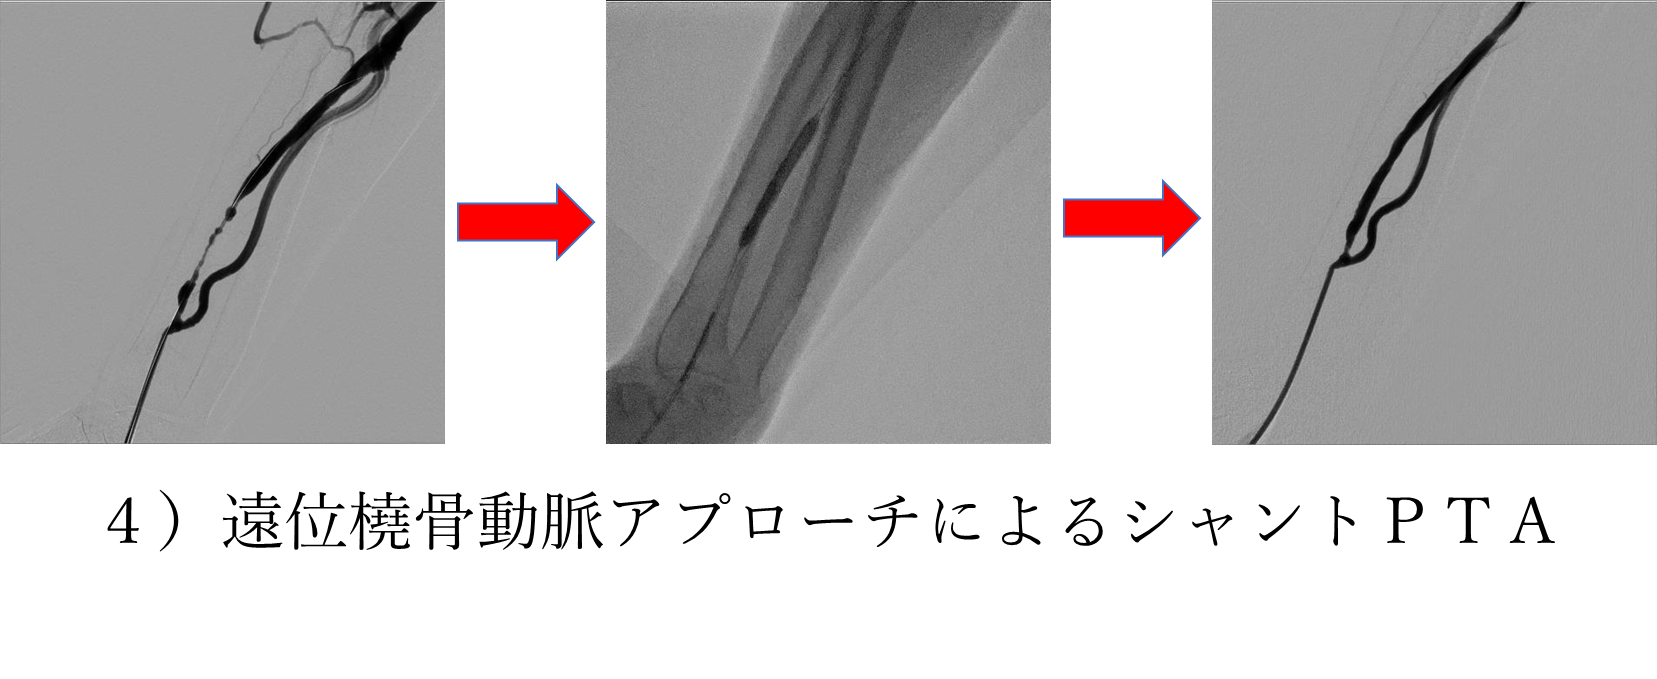

特殊ではありますが、4)のように透析患者様に対してのシャントPTAもできる限り低侵襲でかつ開存期間を少しでも長く延ばせるようカテーテル治療を行っております。